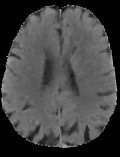

Accurate infarct segmentation in non-contrast CT (NCCT) images is a crucial step toward computer-aided acute ischemic stroke (AIS) assessment. In clinical practice, bilateral symmetric comparison of brain hemispheres is usually used to locate pathological abnormalities. Recent research has explored asymmetries to assist with AIS segmentation. However, most previous symmetry-based work mixed different types of asymmetries when evaluating their contribution to AIS. In this paper, we propose a novel Asymmetry Disentanglement Network (ADN) to automatically separate pathological asymmetries and intrinsic anatomical asymmetries in NCCTs for more effective and interpretable AIS segmentation. ADN first performs asymmetry disentanglement based on input NCCTs, which produces different types of 3D asymmetry maps. Then a synthetic, intrinsic-asymmetry-compensated and pathology-asymmetry-salient NCCT volume is generated and later used as input to a segmentation network. The training of ADN incorporates domain knowledge and adopts a tissue-type aware regularization loss function to encourage clinically-meaningful pathological asymmetry extraction. Coupled with an unsupervised 3D transformation network, ADN achieves state-of-the-art AIS segmentation performance on a public NCCT dataset. In addition to the superior performance, we believe the learned clinically-interpretable asymmetry maps can also provide insights towards a better understanding of AIS assessment. Our code is available at https://github.com/nihaomiao/MICCAI22_ADN.